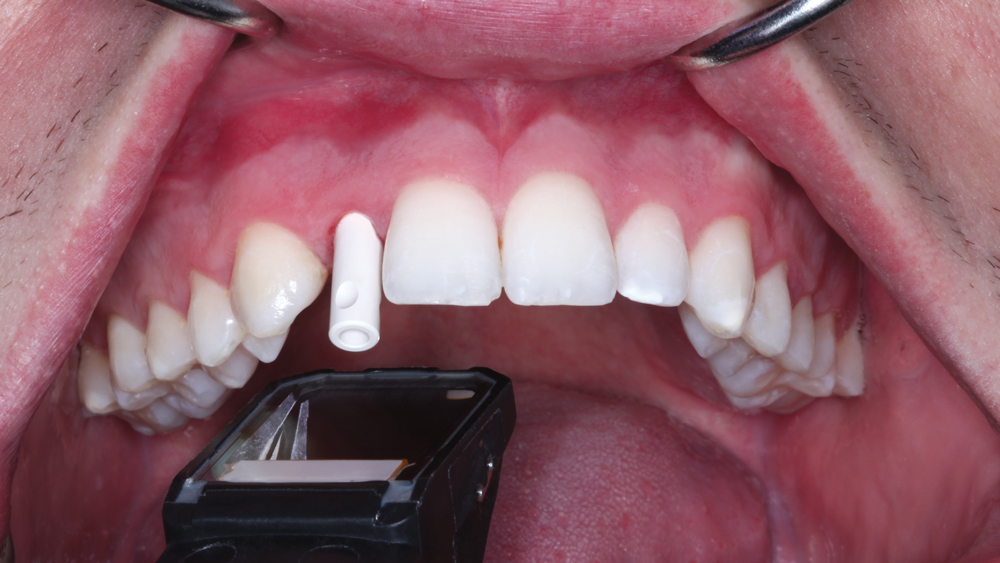

The following case illustrates the efficient, straightforward clinical workflow for placing Hahn Tapered Implants via guided surgery. A digital treatment plan is developed in which a 3.5 mm implant is positioned to support the ideal prosthetic outcome. An immediate provisional crown is designed in concert with the surgical guide and delivered at the time of surgery, helping to produce a predictable, highly esthetic restoration for a demanding case in the smile zone.